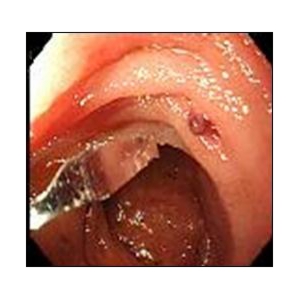

食道アカラシアとは下部食道括約筋の異常により、下部食道狭窄、下部食道弛緩不全が起こり、食事が食道から胃へスムーズに流れない病態です。薬物療法や、内視鏡的バルーン拡張術では治療効果が乏しいことが多く、一般的には根治術として外科手術(Heller-Dor法)が行われています。外科手術にて行ってきた筋層切開術を、内視鏡的に行ったものがPOEMであり、その有用性より外科手術に替わる標準術式になりつつあります。POEMは2008年に井上晴洋先生により初めて報告された処置であり、当科では2010年11月に導入し、計11例の症例に対して施行し、良好な治療成績を得ております。

《POEMの実際》

《POEM前後の比較》